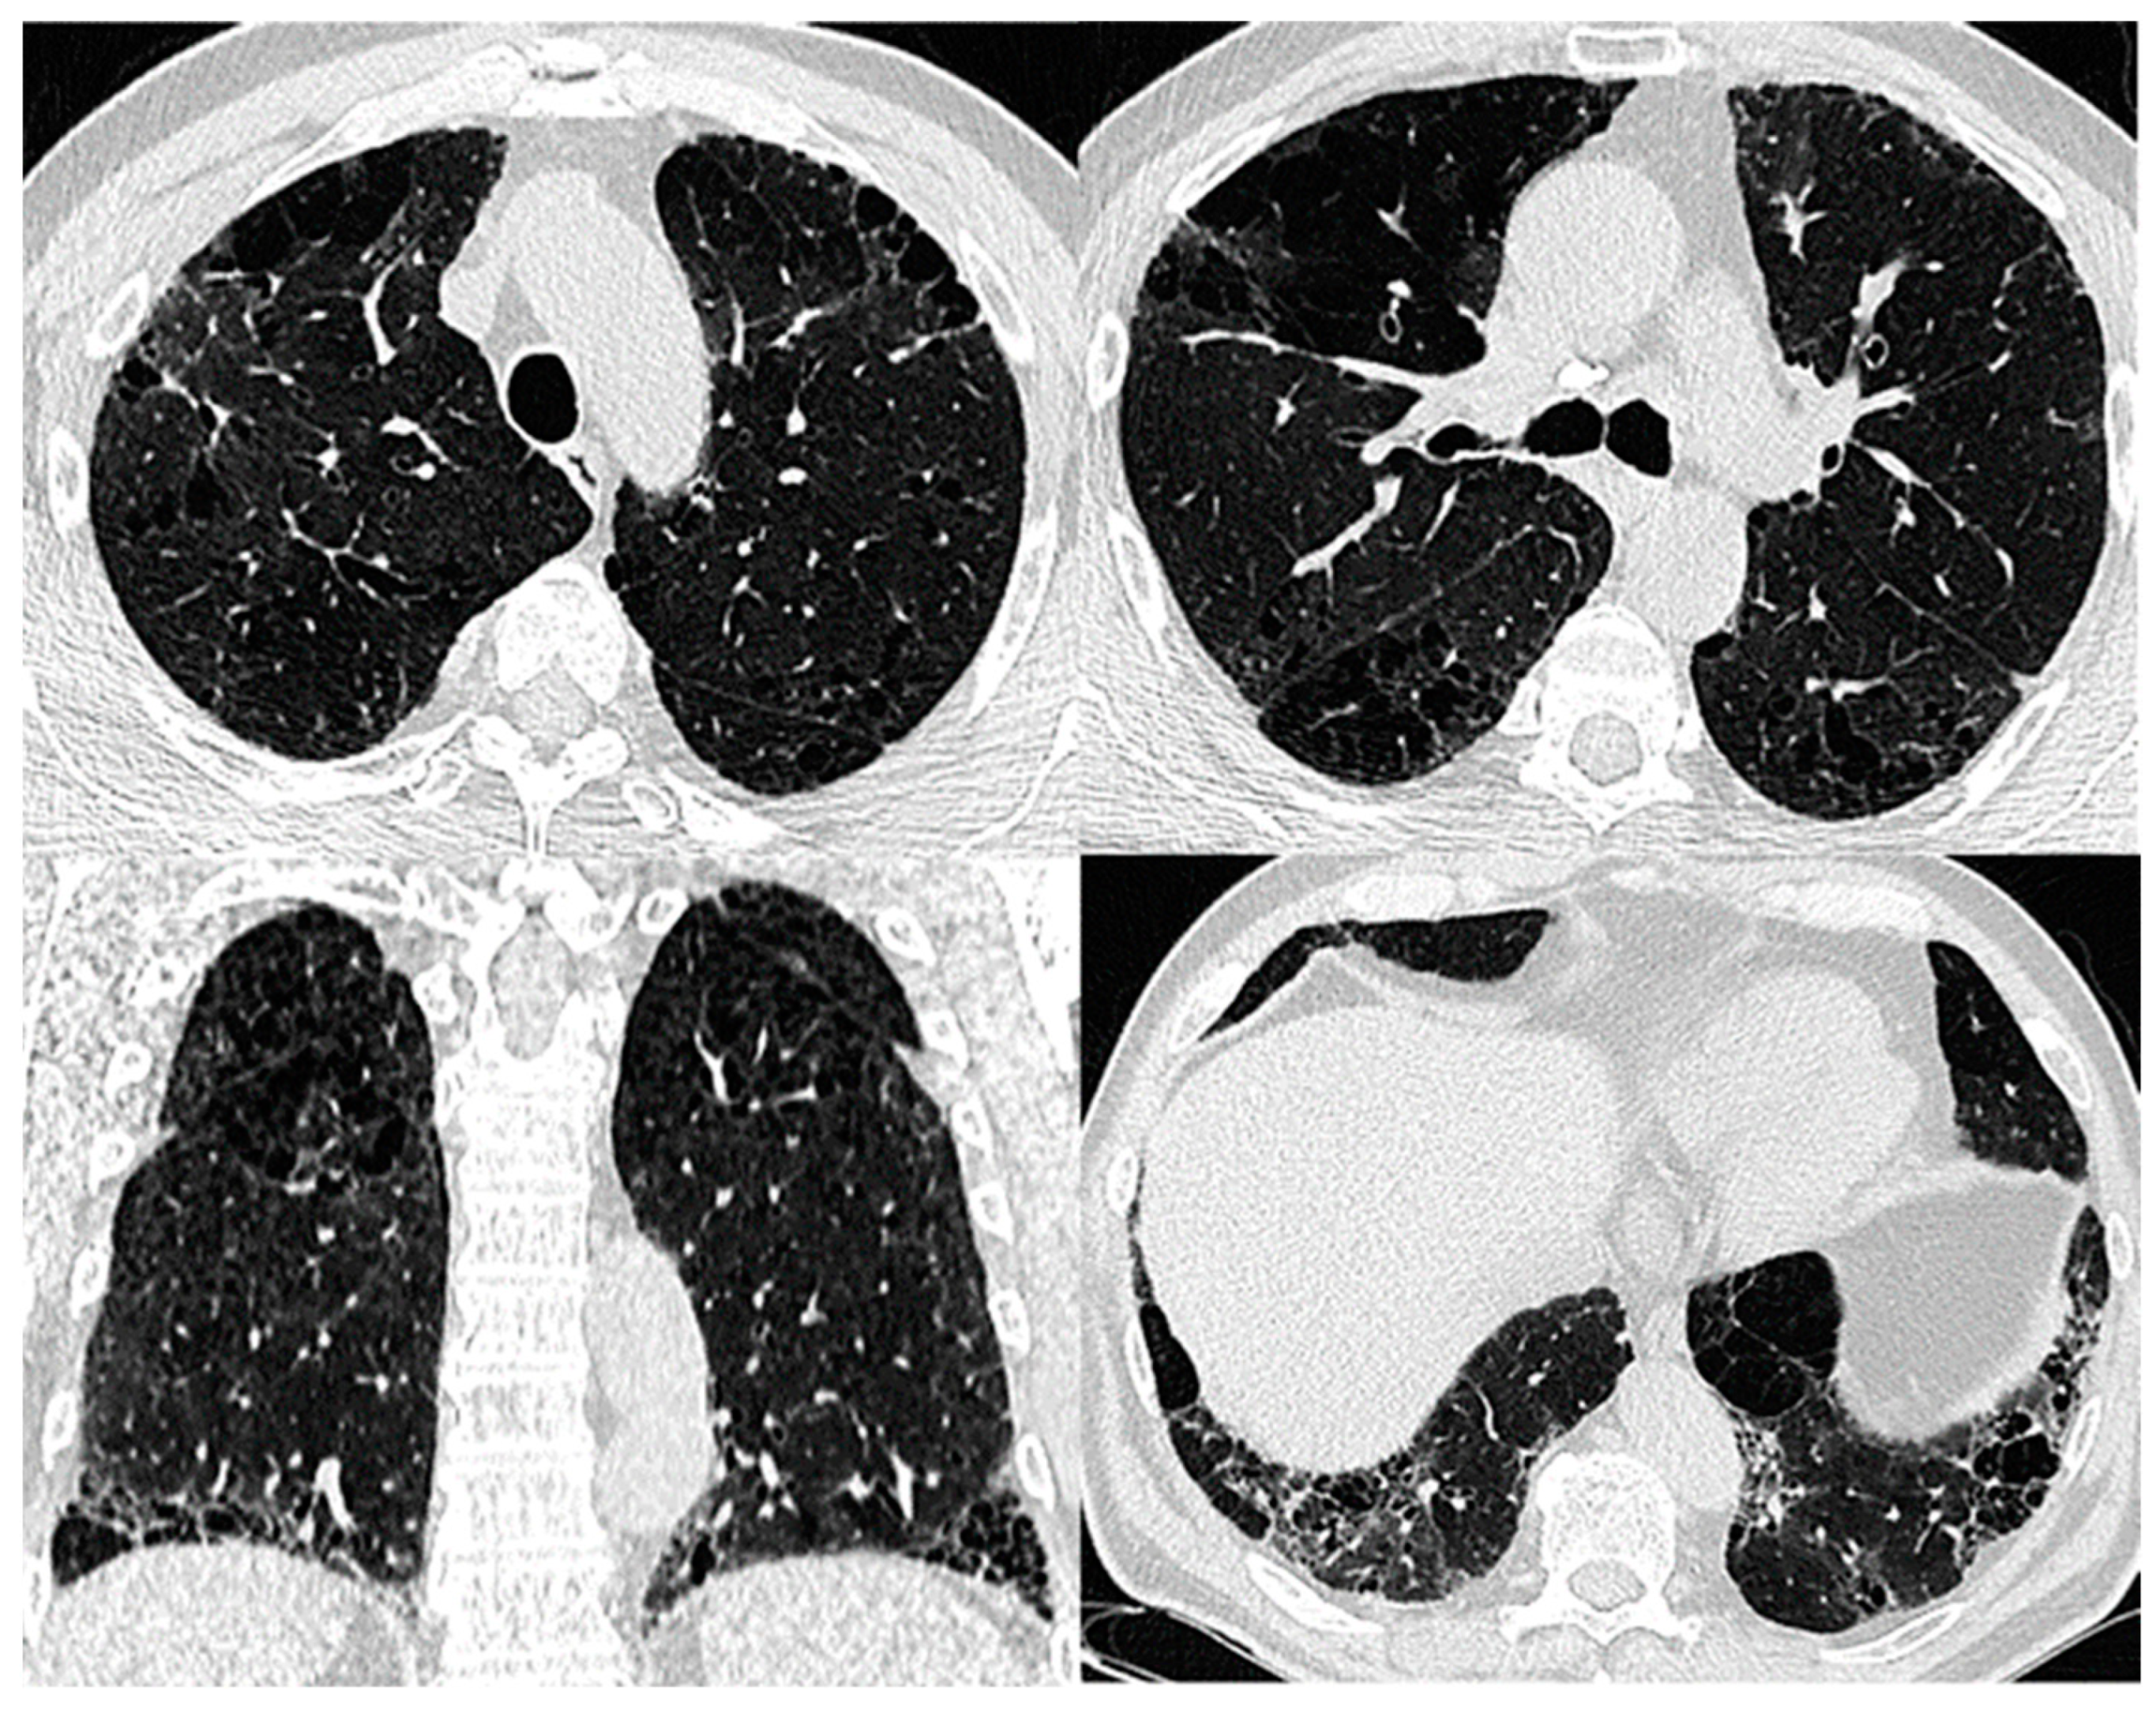

7. Lung Function

| Imaging | Centrilobular and/or bullous emphysema | Coexistence of paraseptal emphysema in the upper zones of the lungs and the UIP/NSIP/DIP in the lower zones, thick-walled cysts in the area of fibrosis | UIP pattern |